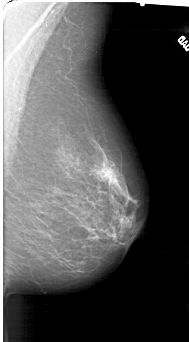

A_1415_1.RIGHT_MLO

LEFT_MLO LINES 6316 PIXELS_PER_LINE 3151 BITS_PER_PIXEL 12 RESOLUTION 43.5 OVERLAY